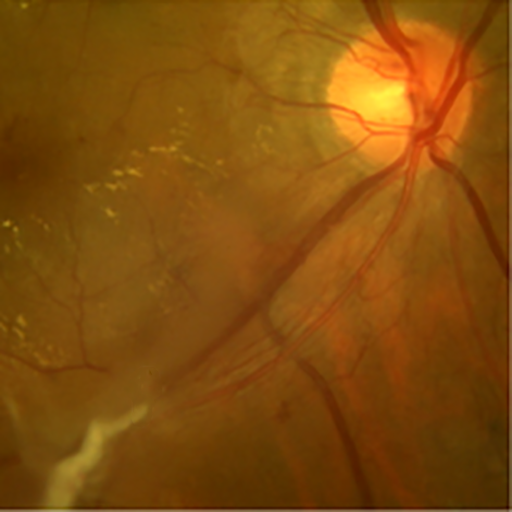

the angio-fibrotic switch in pdr